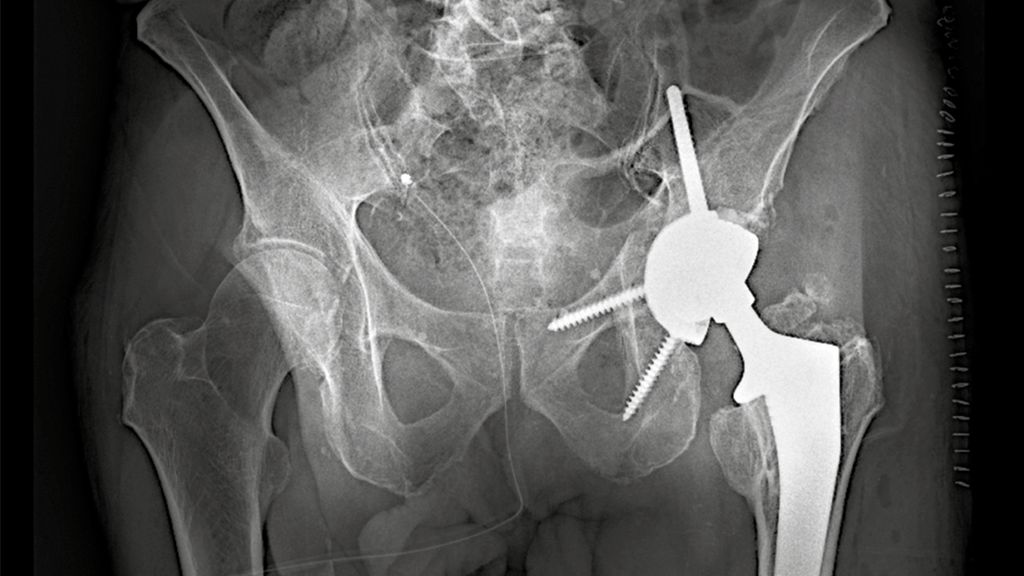

Implantation der PRS-Rekonstruktionspfanne

Die PRS-Pfanne zeichnet sich durch ihre massive Bauweise, multiple Schraubenoptionen und die Möglichkeit einer zentralen Ileumschraube aus. Nach Einbringen der Pfanne wird diese korrekt ausgerichtet (Inklination ca. 40–45°, Anteversion ca. 15–20°). Der entscheidende Schritt ist die Platzierung der zentralen Ileumschraube. Dafür wird unter Bildwandlerkontrolle ein Bohrdraht in den supraazetabulären Korridor gesetzt (Abb. 3a u. 3b) und mit dem 6-mm-Bohrer überbohrt. Anschließend wird die Schraube durch das entsprechende Positionsloch der Pfanne in den supraazetabulären Anteil des Iliums eingebracht. Dabei ist auf eine ausreichende Schraubenlänge zu achten, um eine stabile Verankerung zu erzielen. Die zentrale Schraube übernimmt eine lasttragende Funktion und wirkt wie eine intrapelvine Abstützung. Zusätzlich wird die Pfanne mit Schrauben im Sitzbein und/oder dem Schambeinast fixiert (Abb. 4). Die PRS-Pfanne erlaubt hierbei eine flexible Schraubenplatzierung, was insbesondere bei komplexen Frakturmorphologien von Vorteil ist.

Dank der hohen Primärstabilität der Konstruktion wird eine frühfunktionelle Behandlung angestrebt. Die Patient:innen können unter physiotherapeutischer Aufsicht vollbelastend mobilisiert werden. Dies stellt einen wesentlichen Vorteil gegenüber der alleinigen Osteosynthese dar, insbesondere bei geriatrischen Patientinnen und Patienten. Eine radiologische Verlaufskontrolle wird postoperativ sowie nach sechs und zwölf Wochen empfohlen.